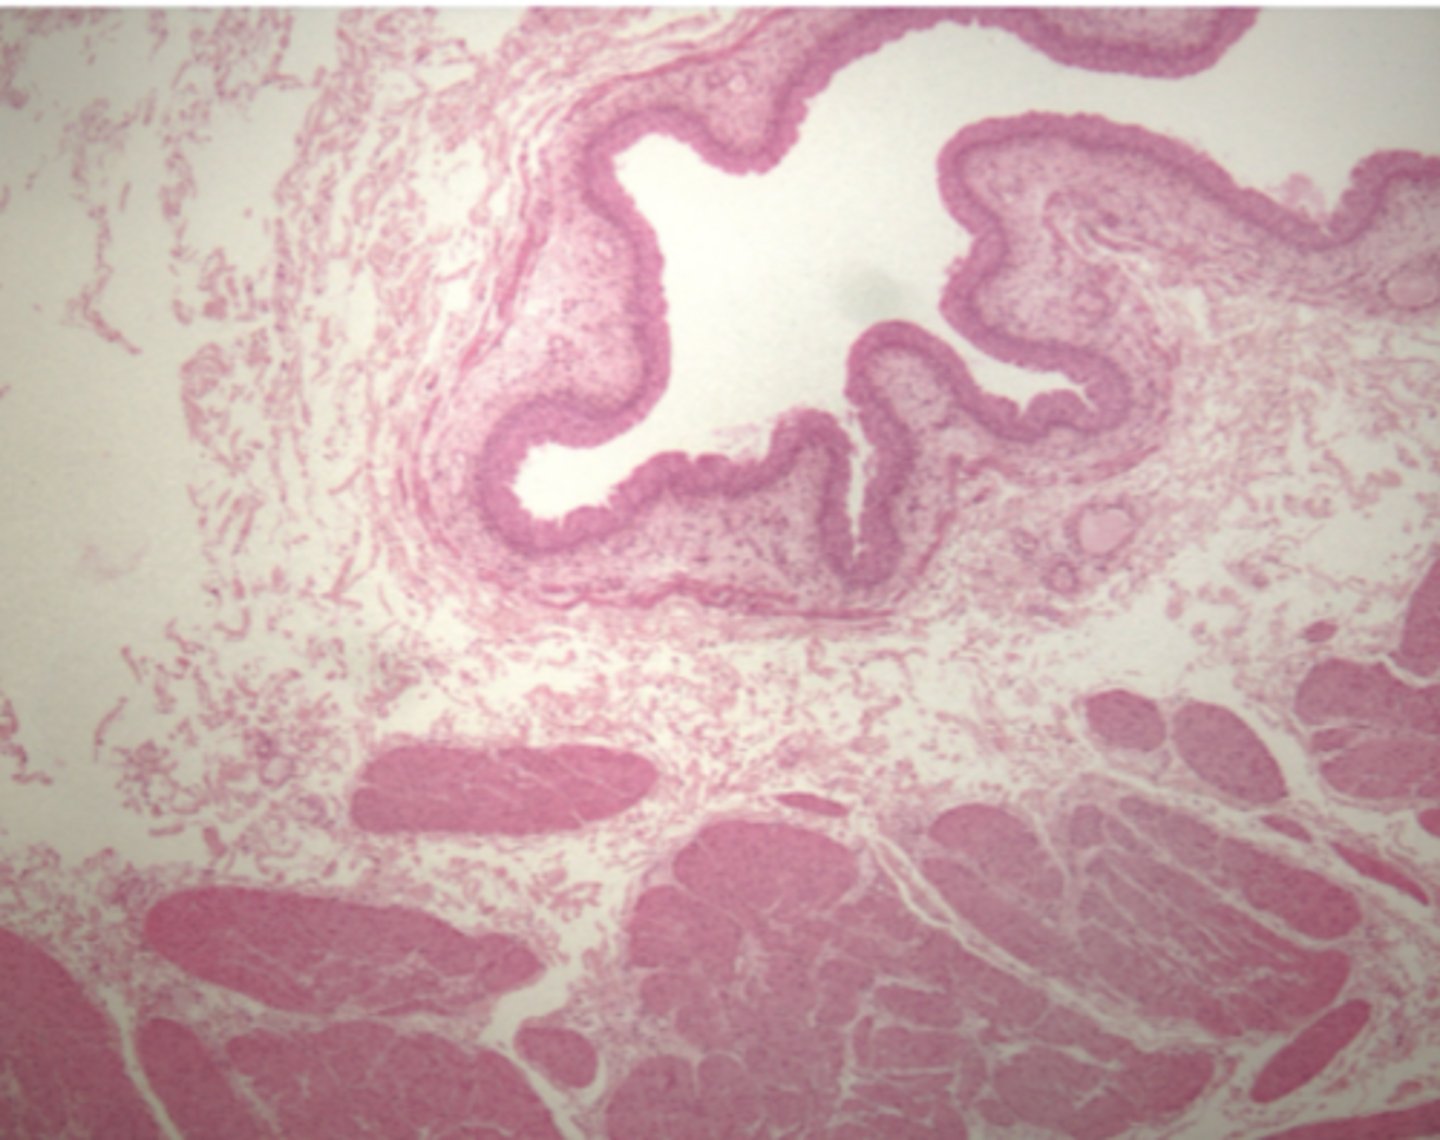

Bladder

What is this?